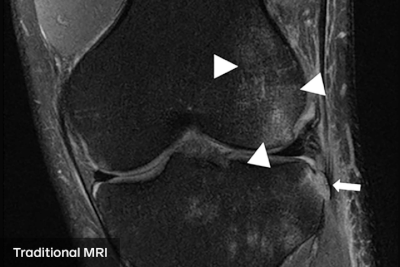

fastMRI团队多年来一直在研究这个问题,但周二他们在《 American Journal of Roentgenology》杂志上发表了一项临床研究,他们说这证明了他们的方法的可信度。该研究要求放射科医生根据传统的核磁共振扫描和人工智能增强的患者膝盖扫描进行诊断。研究报告称,当面对传统扫描和AI扫描时,医生做出的评估完全相同。

“这里可以基于信任的关键词是互换性,”Sodickson说。“我们不是在看一些基于图像质量的量化指标。我们是说,放射科医生做出同样的诊断。他们发现同样的问题。他们不会错过任何东西。”